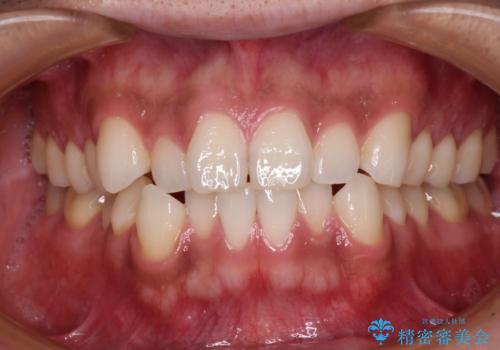

- 上下顎歯列のデコボコを改善したいとのことで来院された患者様です。

自己管理の大変なインビザラインや、目立つ表側のワイヤー矯正は避けたいとのことで、

上顎だけ裏側装置のハーフリンガルにて矯正しました。